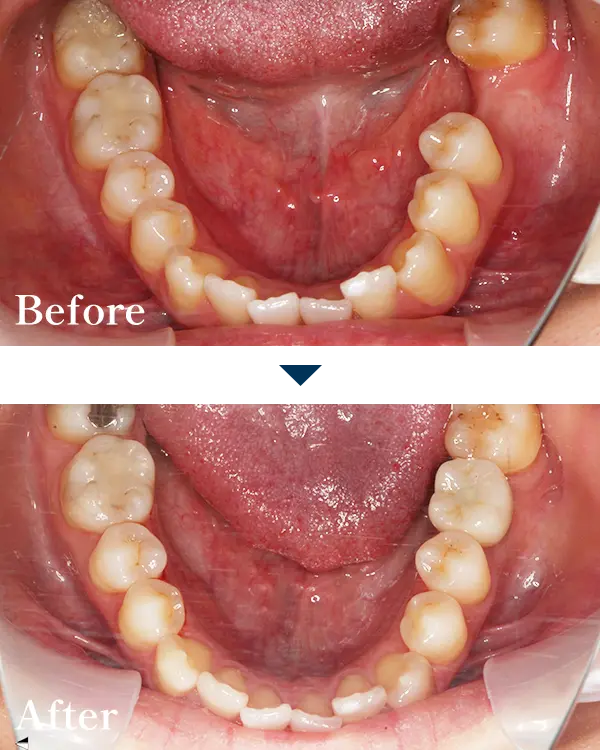

| 主訴 | 奥歯がないので、歯を入れたい |

|---|---|

| 治療内容 | 左下6番にインプラントを埋入し、 ジルコニア上部構造で治療 |

| 治療期間 | 550,000円(税込) |

| 標準費用【自費】 | 約4ヶ月 |